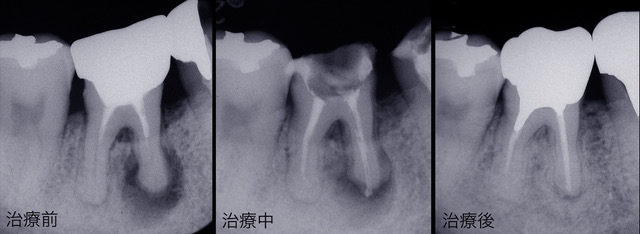

● レントゲン診断

歯科医院でレントゲンを撮って説明を受けたことがあると思います。画像が不鮮明でよくわからなかったという方が多いのではないでしょうか。レントゲンの種類や撮影法、現像法には多くの種類がありそれによって画像の鮮明度には差がでてきます。須貝歯科医院ではレントゲン診断にこだわり鮮明な画像が得られるようにシステムを構築しています。歯科医師自身が位置づけをして撮影を行っていますので以前に撮影したレントゲンと比較して違いを見ることができ、正確な診断がおこなえるようにしています。また撮影されたレントゲンはパソコンのモニター上に拡大し、素人の患者さんが見てもわかるようしています。

左側のレントゲンでは根の先端に大きな病巣があるのがわかります。右側が治療後ですが病巣が消えています。歯を入れるだけでなくレントゲンで骨の状態の改善が確認できなければ本当に治ったとは言えません。